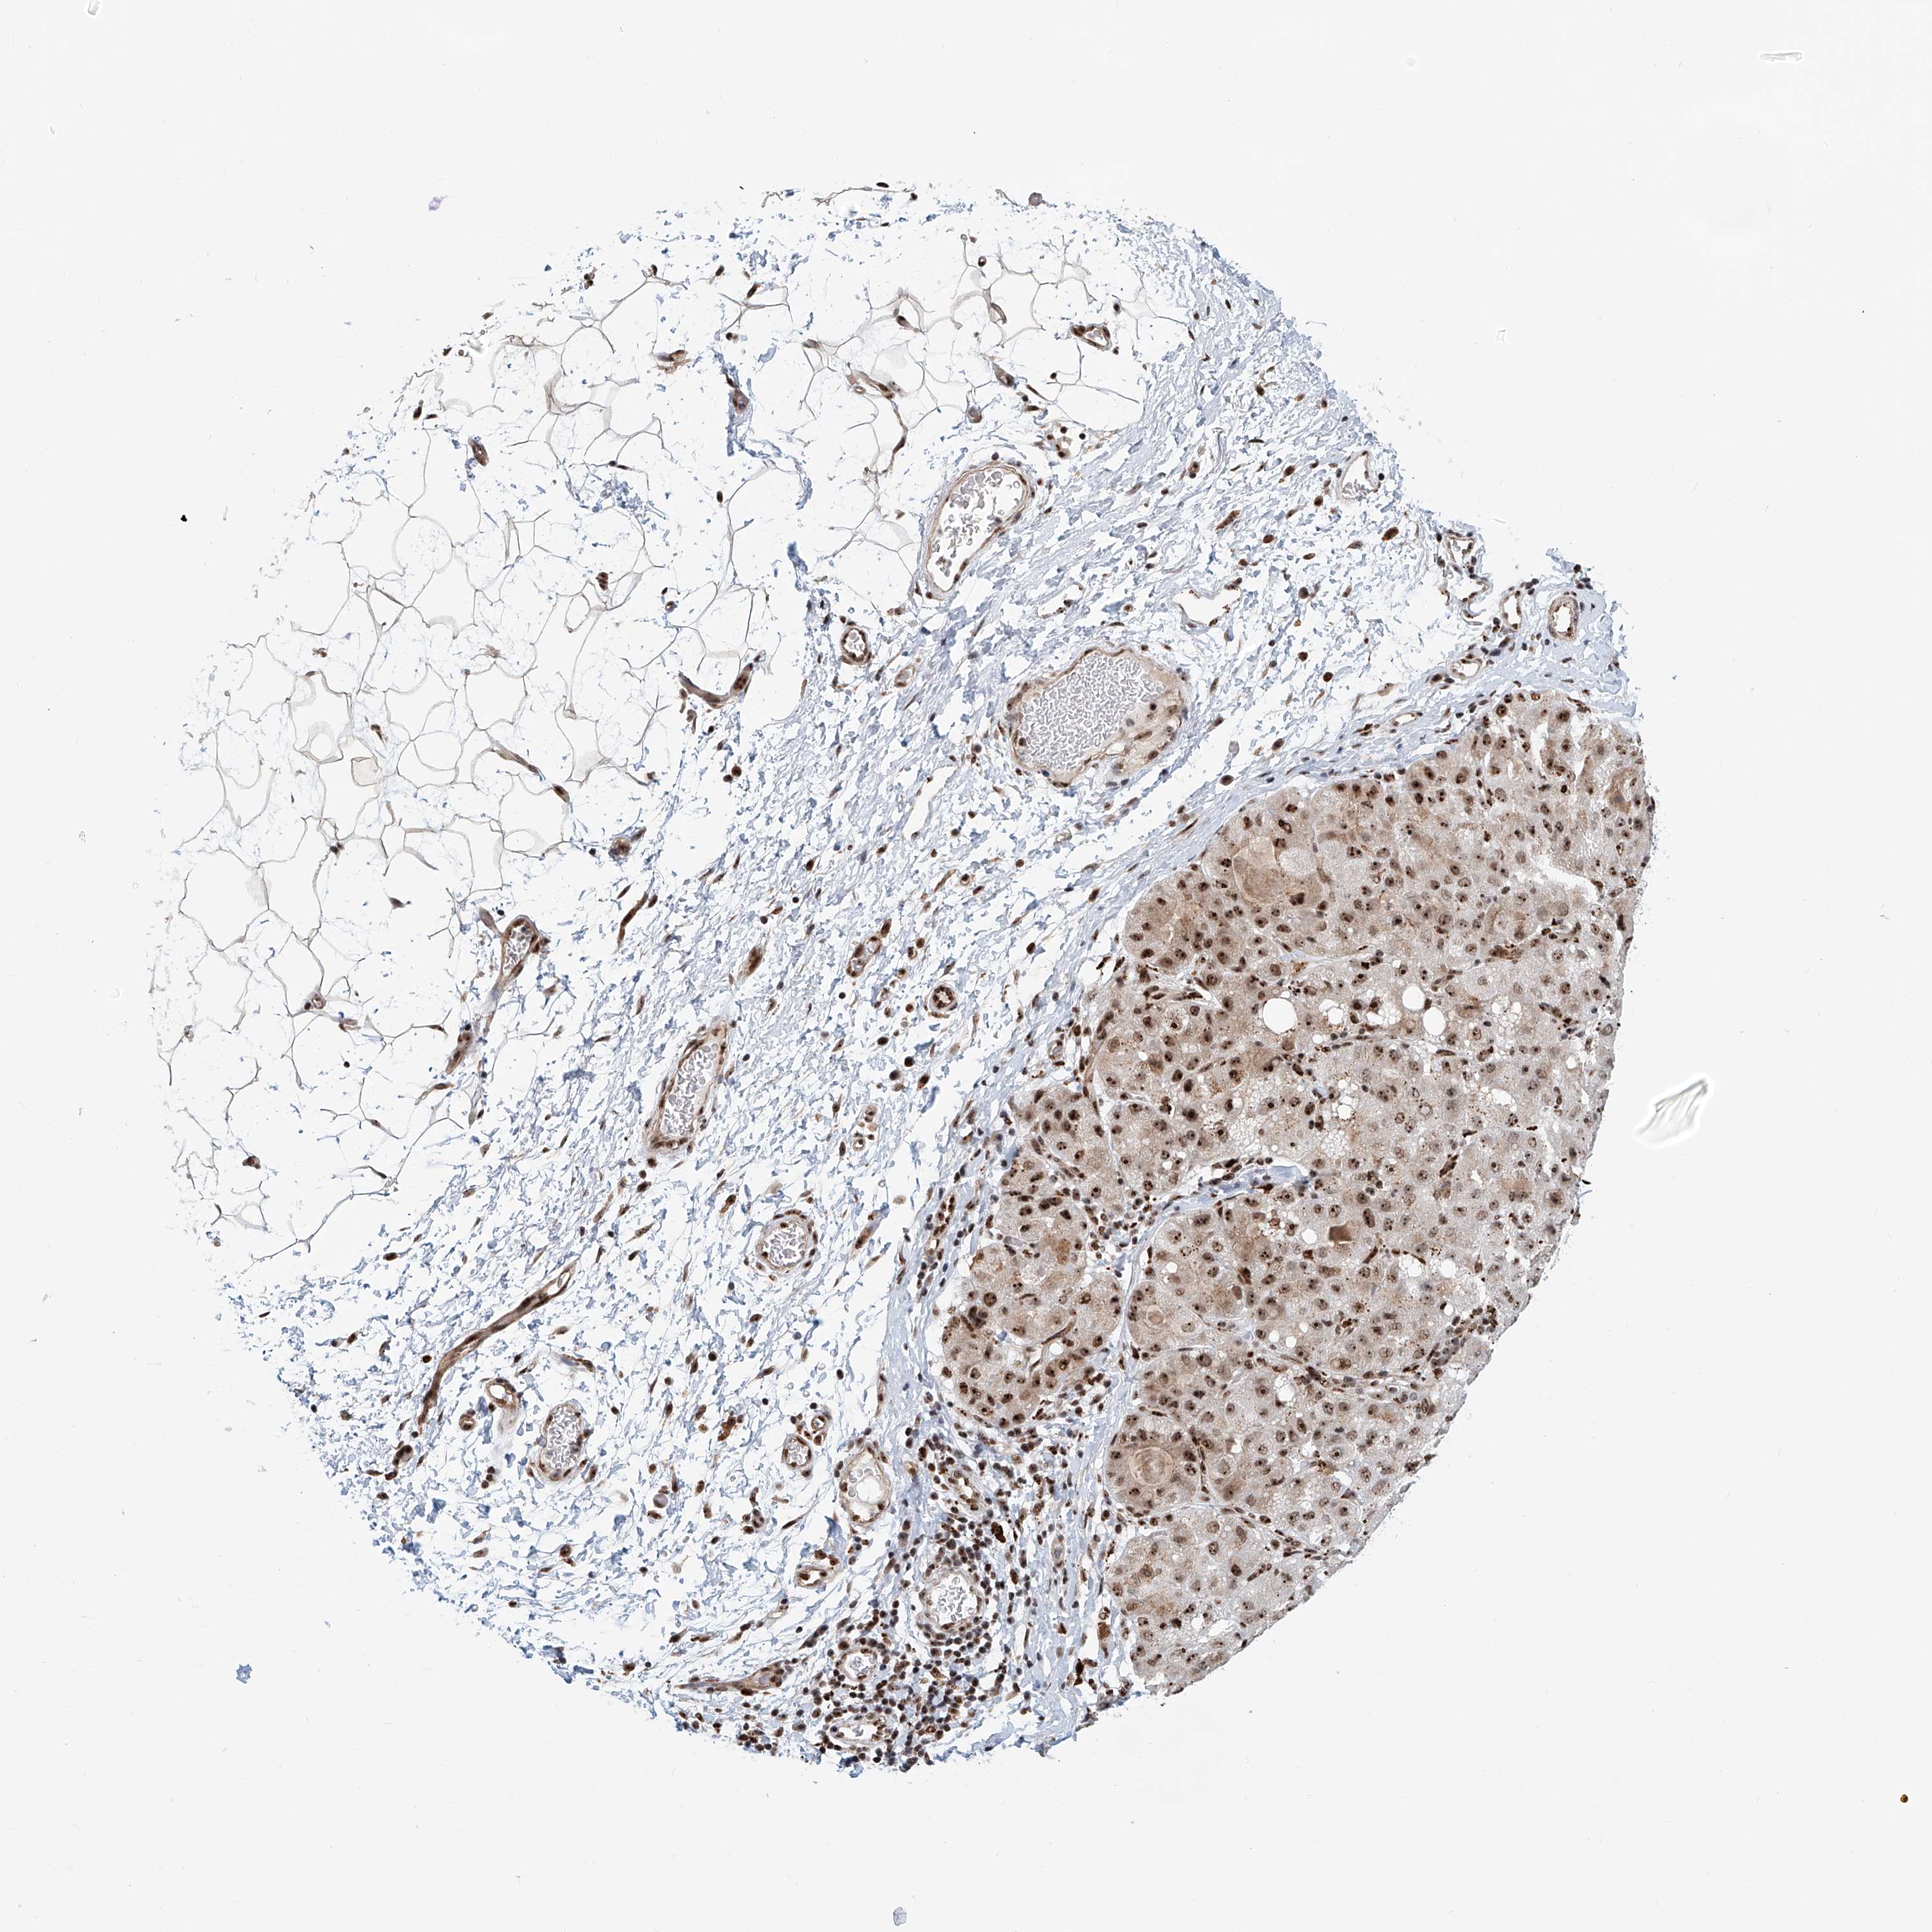

LIVER CANCER - Protein expressioni

A mouse-over function shows sample information and annotation data. Click on an image to view it in a full screen mode. Samples can be filtered based on level of antibody staining by selecting one or several of the following categories: high, medium, low and not detected. The assay and annotation is described here.

Note that samples used for immunohistochemistry by the Human Protein Atlas do not correspond to samples in the TCGA dataset.

Antibody stainingi

Antibody staining in the annotated cell types in the current human tissue is reported as not detected, low, medium, or high, based on conventional immunohistochemistry profiling in selected tissues. This score is based on the combination of the staining intensity and fraction of stained cells.

Each image is clickable and will lead to virtual microscopy that enables deeper exploration of all samples and also displays staining intensity scores, fraction scores and subcellular localization as well as patient and tissue information for each sample.

Antibody HPA022470

Antibody HPA031079

Staining

High

Medium

Low

Not detected

Intensity

Strong

Moderate

Weak

Negative

Quantity

>75%

75%-25%

<25%

None

Location

Nuclear

Cytoplasmic/membranous

Cytoplasmic/membranous,nuclear

Cholangiocarcinoma

Carcinoma, Hepatocellular, NOS